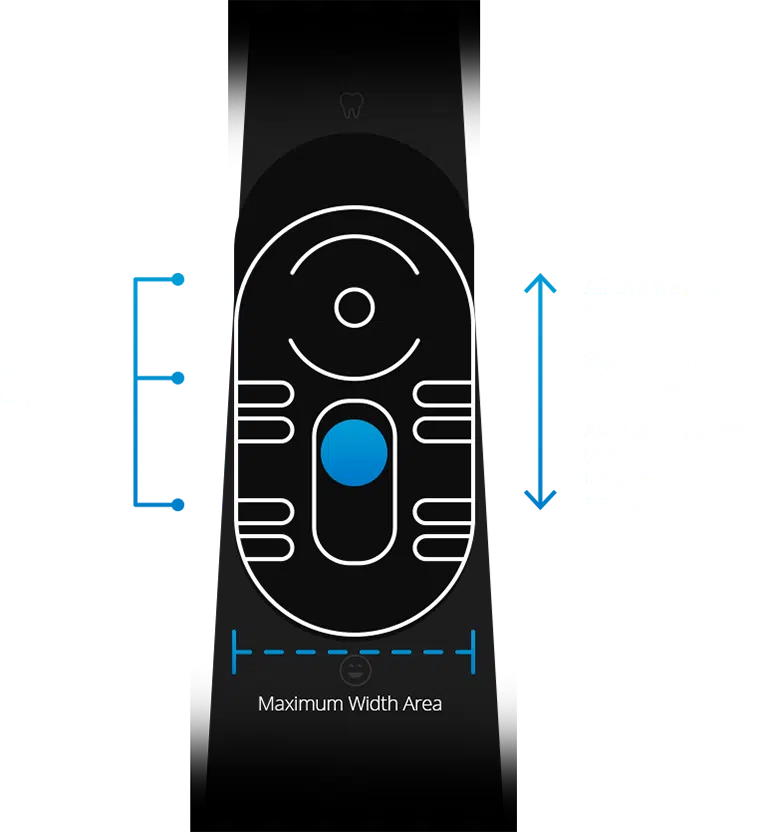

Intraoral Camera

Claris i5HD

25 years of intraoral camera evolution. Native 1080p HD sensor, space-grade anodized aluminum body, and less than 5% lens distortion. Turnkey integration with every major platform.

"The extra-large slide-focus makes adjusting focus super easy and quick especially when handling the camera on-the-fly."